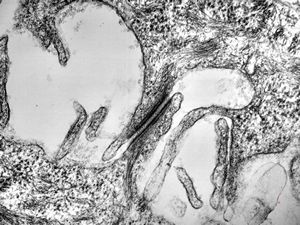

oral saprophytic bacterium